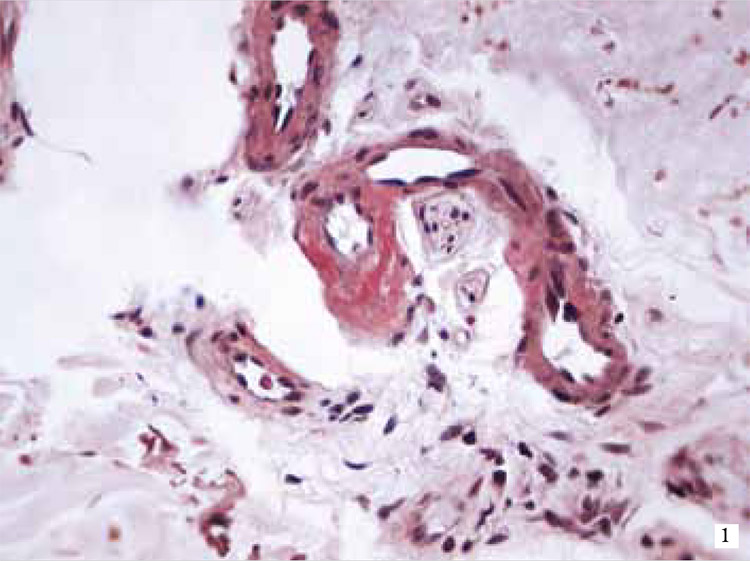

Haga usted el diagnóstico. Parte 1

Haga usted el diagnóstico. Parte 2